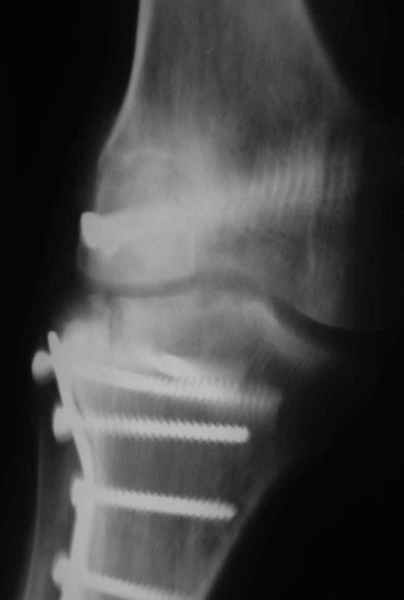

Как вариант решения прогрессирующей вальгусной деформации коленного сустава я бы предложил косую остеотомию дистального отдела бедра с фиксацией пластиной и компрессирующим винтом.

Взгляните на снимки , может быть это вам поможет.

Около 5 лет применяю этот тип дистальной остеотомии бедра для коррекции механической оси Н/К ( более 20 случаев) - достаточно эффективная операция.

На своем горьком опыте убедился, что синтезировать мыщелковые импрессионные внутрисуставные переломы б\б кости без костной пластики - дело неблагодарное, рецидивируе деформация, мыщелок всегда *проваливается*. Чистые split type переломы можно ограничиваться и одной только межфрагментарной компрессией.

Может стоит сначала добиться сращения наружного мыщелка бедра( костная пластика) и коррекции оси?

Мне представляется, что прогрессирующий вальгус и обусловлен несросшимся переломом мыщелка бедра (томограммы -зона межфрагментарного склерозирования), а циклические нагрузки на сустав во время ходьбы усугубляют ситуацию. Как вы думаете, в этой ситуации насколько вероятен риск развития аваскулярного некроза мыщелка бедра?